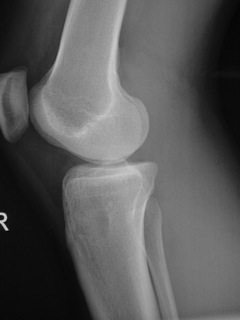

• Lytic lesion (Fig. 1, Fig. 2 & Fig. 3)

• Well-defined

• Geographic margins

• Eccentric

• Majority have well-defined sclerotic rims

• More aggressive lesions may have irregular margins

• Frequently produce endosteal erosion and cortical thinning

• Trabeculation may be seen

Fig. 2

Fig. 1-3: AP and Lateral plain x-rays of a benign fibrous histiocytoma shows an eccentric lytic lesion in the proximal tibia, well- demarcated with a prominent sclerotic rim. No soft tissue mass or trabeculations are seen.